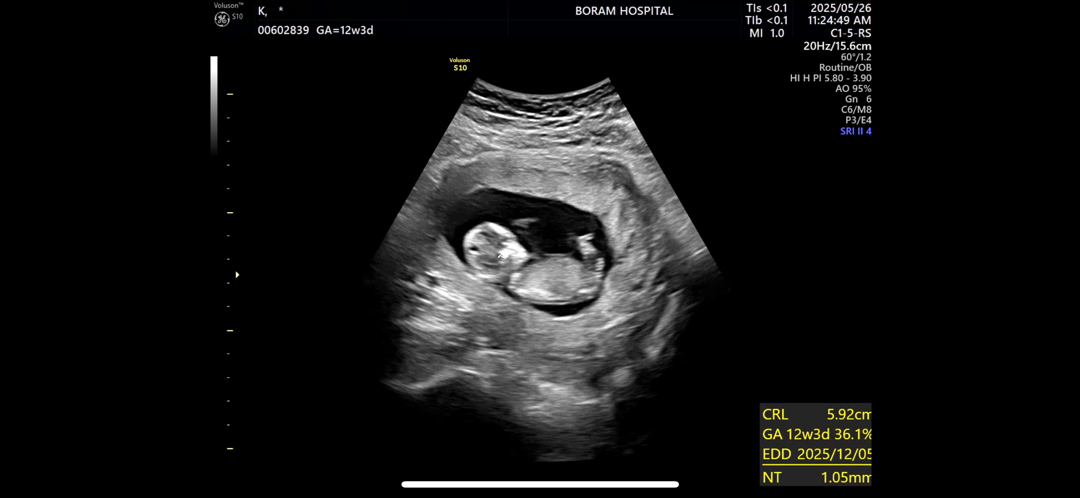

각도법 잘 아시는 분 계신가여🥹🥹

남편에게 젠더리빌 약속하고 성별 검사일만 기다리는 중인데 시간이 넘 안 가네요ㅜㅜ 각도법 잘 보시는 분 혹시 딸인지 아들인지 보이시나요…??🫣🫣